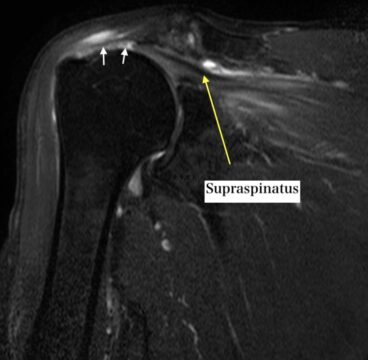

A physician will usually evaluate the shoulder with a physical examination and imaging such as MRI (Figure 2) or ultrasound to check whether a rotator cuff injury is present.

Ultrasound has been reported to be useful for diagnosing rotator cuff tears, and MRI is also widely used. The choice of imaging depends on the clinical setting and the question being asked[3][4].

The clinical exam also includes the history of the problem, palpation, and muscle-specific testing. For example, supraspinatus testing helps assess elevation strength, infraspinatus testing helps assess external rotation strength, and subscapularis testing helps assess internal rotation strength.